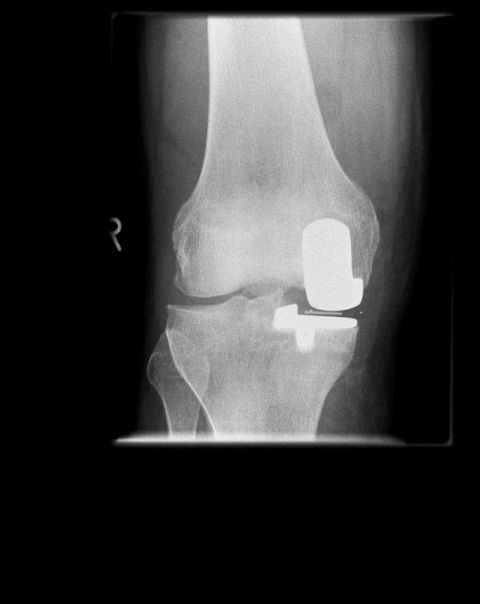

GEKOPPELTE KNIEENDOPROTHESEN

Bei ausgeprägteren Knochendefekten am Schienbeinkopf oder ausgeleierten Bändern muss in den meisten Fällen dem Verlust der Bandstabilität Rechnung getragen werden und durch das künstliche Gelenk selbst die Stabilisation des Gelenkes übernommen werden. Hierzu eignen sich teil- oder vollgekoppelte Kniegelenke. Diese künstlichen Gelenke müssen die auftretenden Kräfte über Stiele  längerstreckig in den Knochen einleiten, da sie ansonsten Gefahr laufen auszulockern. Der dazu notwendige Hautschnitt unterscheidet sich nicht von den sonst üblichen.

Solche Prothesen sind oft im Rahmen der Revisionsendoprothetik notwendig.

Die 64 jährige Friseurin, Rheumatikerin, wurde im Juli 2020 mit einem bakteriellen Infekt im Kniegelenk stationär aufgenommen. Sie konnte schon seit längerer Zeit nicht mehr richtig laufen. Das Knie war instabil und kaum noch belastbar bei ausgeprägten Knochendefekten. Die Behandlung zielte zunächst auf die Sanierung des Infektes bei septischem Krankheitsbild. Im Verlauf der Behandlung entwickelte die Patientin zudem eine akute Gallenblasenentzündung, die durch die Abteilung für Allgemeinchirurgie im Hause operativ behandelt werden musste. Zudem wurde ein Infektionsherd im Bereich der Nasennebenhöhlen durch einen operative Intervention der Gesichtschirurg*innen behandelt.

In einem zweiten stationären Aufenthalt, nachdem die Patientin wieder zu Kräften gekommen war, wurde dann im Oktober ein künstliches Kniegelenk eingesetzt. Die erhebliche Knochendefektsituation, sowohl auf der Oberschenkel als auch Unterschenkelseite, wurde durch ein spezielles Revisionsknie mit Ausgleich der knöchernen Defekte über Metallaufbauten bewerkstelligt. Die Patientin erholte sich weiter und arbeitet inzwischen wieder als Friseurin in Ihrem Salon.